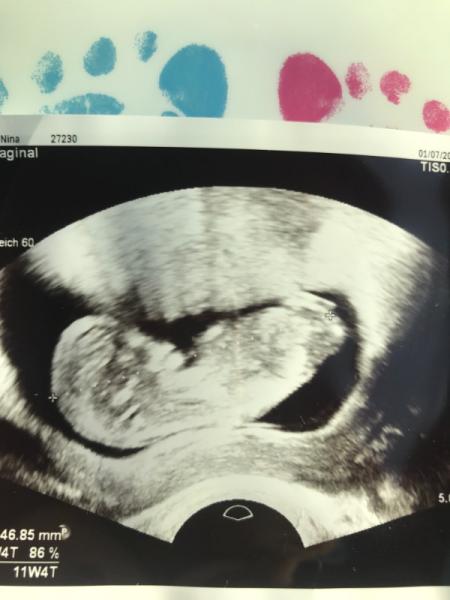

Hallo zusammen, wollte mich mal den vielen guten Nachrichten diese Woche anschließen und mit Euch teilen dass auch mein FA Termin gestern wunderschön verlief. Das kleine ist von 1cm (letztes mal vor 3 Wochen) auf 4,7 cm gewachsen, hat fleißig gestrampelt und als ich die Herztöne zum ersten mal HÖRTE, hatte ich Tränen in den Augen. ICH - die bis 34 (bin jetzt 36) felsenfest ihr Leben lang gesagt hat, dass mir Kinder zu viel sind und ich lieber ein Leben ohne diese Belastung will Also ich bin einfach dankbar dass alles gut ist und die ersten 3 Monate (auch voller innerer Zweifel) endlich rum . Habs nun in die welt posaunt und alle (bis auf 3 sehr enge Menschen) sind fast vom Stuhl gefallen Wie macht ihr das mit Pränataldiagnostik? Wir überlegen, zuerst den Harmony Test (und nen ultraschall) machen zu lassen, KEINE Fruchtwasseruntersuchung. Der Ultraschall/Nackenfaltenmessung ist trotz meines alters KEINE Leistung der Kasse, sagte die ärztin ?! Liebe Grüße